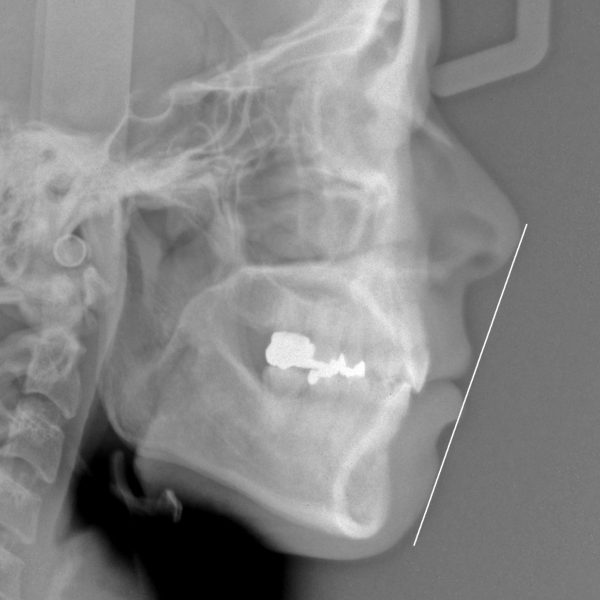

レントゲン写真を 見てみましょう

前歯が 強く傾斜していて、くちびるを押し出していることが分かります

治療前後で前歯の傾斜がかなり改善しました。

レントゲン写真で確認しても上下の前歯は 大きく下がり、

前に出ていた上下の前歯の傾きが正常化しました。